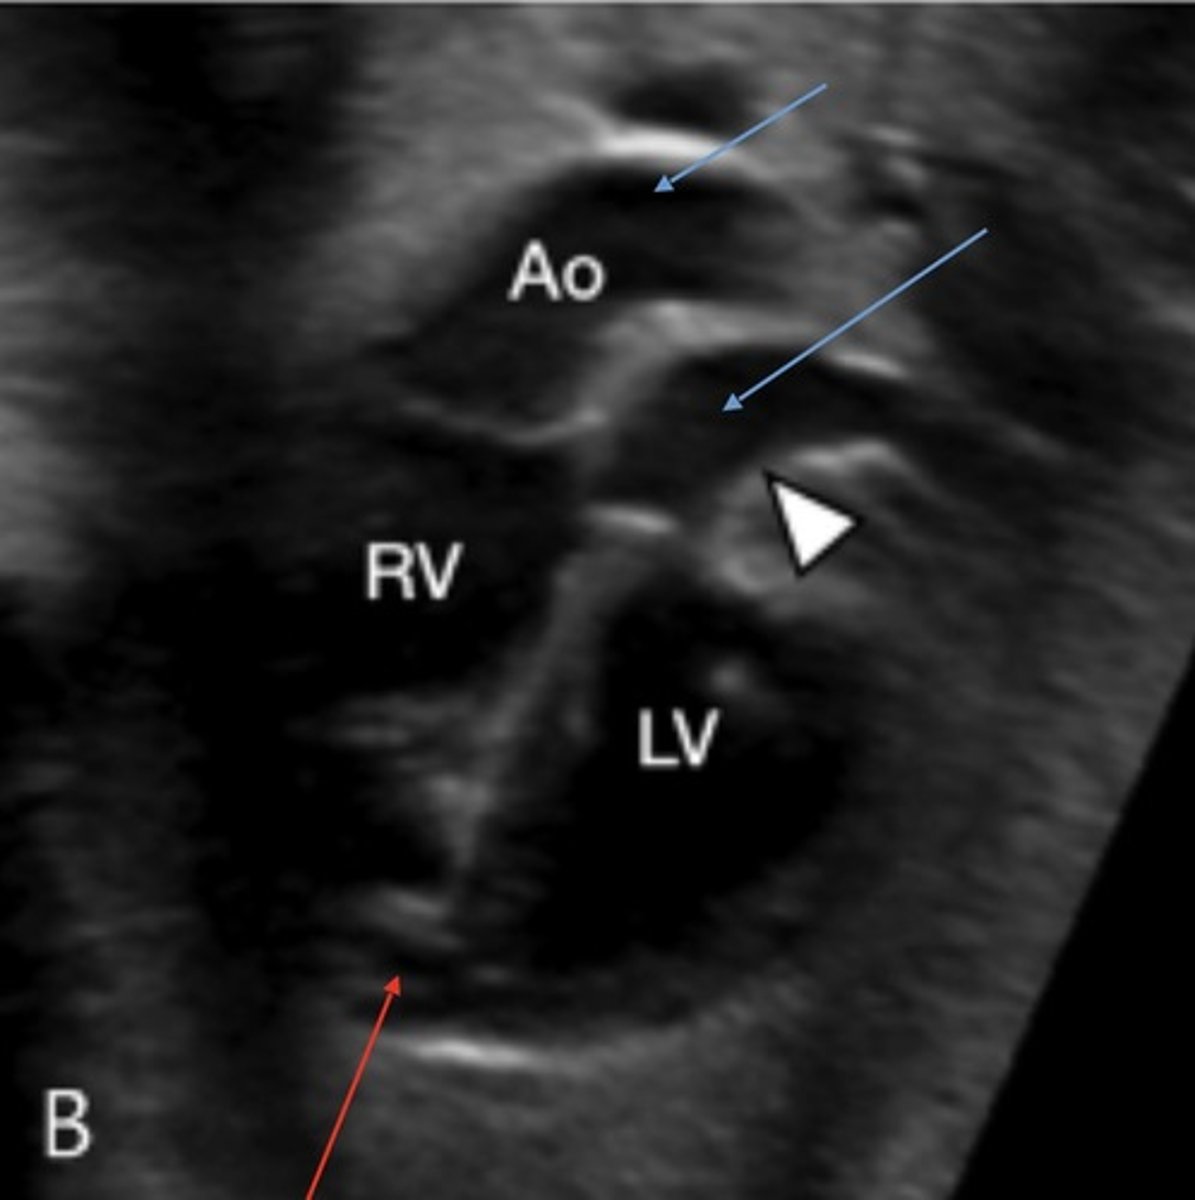

Truncus Arteriosus

Best seen in LVOT view

Truncoconal ridge fails to fuse

Appears as single great vessel with VSD